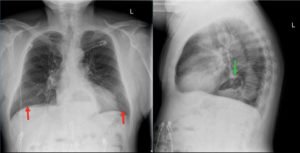

The two-view chest X-ray shows mild opacification of the bilateral lower lobes concerning for pneumonia (red arrows). Incidental retrocardiac opacity with air-fluid level consistent with large hiatal hernia is also observed (green arrow).

In this case, the chest X-ray was concerning for pneumonia, and a large, incidental hiatal hernia was also appreciated. Patient was started on antibiotics for the pneumonia and admitted to internal medicine. The hiatal hernia was not operated on because the patient was asymptomatic.